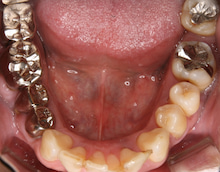

写真からは わかりにくいですが、

奥歯は歯周病のため ぐらぐらしています。

残念ながら 奥歯 2本は

抜かざるを得ない状況です。